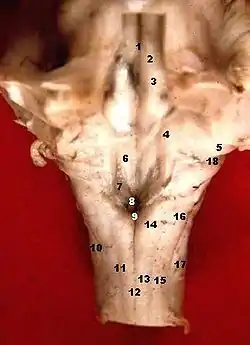

![]() Human caudal brainstem posterior view description (Area postrema is #8) | |